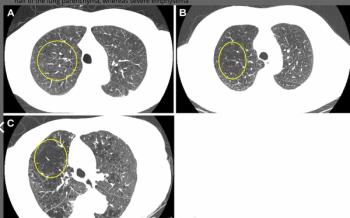

In a recent interview with Diagnostic Imaging, Noa Antonissen, M.D., and Colin Jacobs, Ph.D., discussed new research findings demonstrating robust risk stratification with a CT-based deep learning model for lung nodules as well as a 39.4 percent reduction in false positives in comparison to traditional classification.

Researchers also found that low-dose chest CT detection of emphysema was associated with a 29 percent higher risk of all-cause mortality up to 25 years later, according to a study involving over 9,000 individuals with a history of smoking.